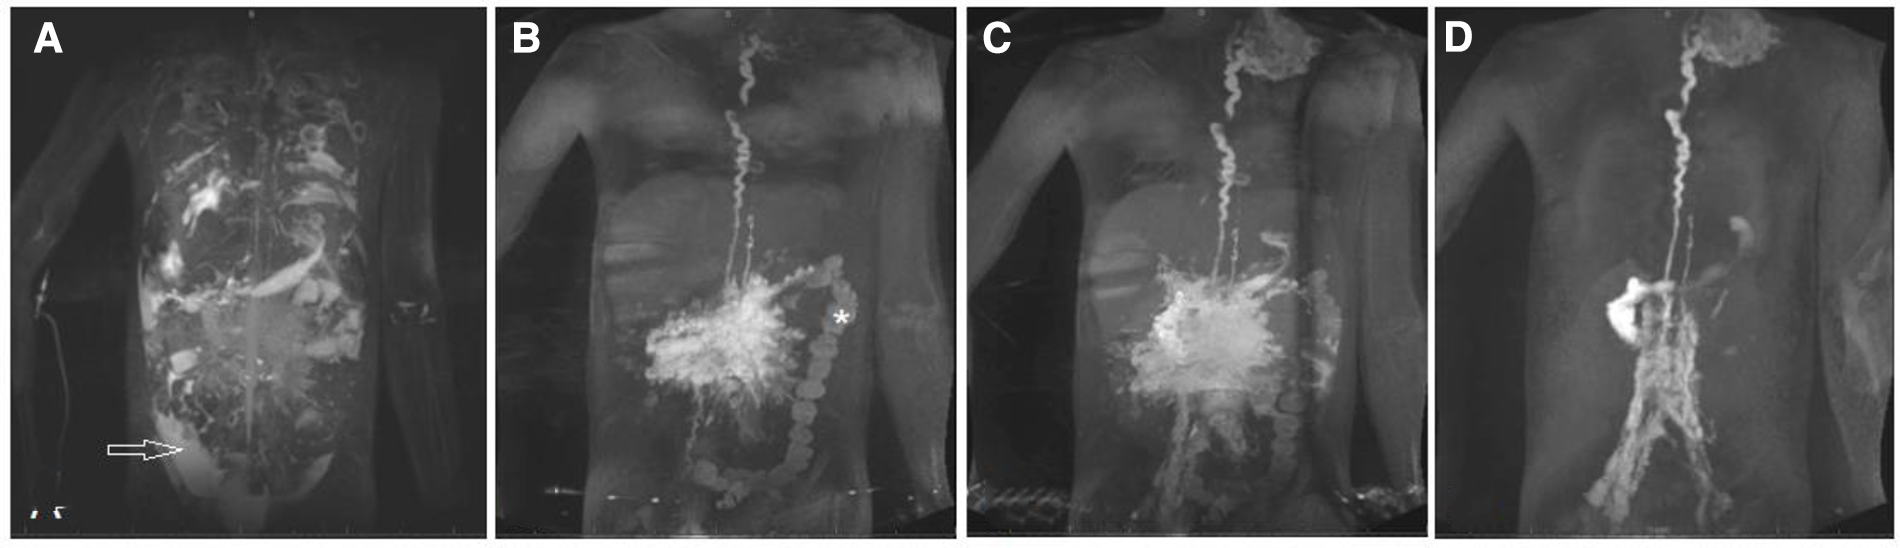

Protein losing enteropathy is the most common lymphatic flow disorder in the abdomen and affects 5%–12% (40, 41) of Fontan patients. Intrahepathic and intramesenteric dynamic contrast magnetic resonance lymphangiography recently demonstrated abnormal increased lymphatic flow from the liver lymphatics (Figures 4A,B) or to a lesser extend from the mesenterial lymphatics (Figures 4C,D) to the duodenum in these patients (42, 43). Duodenal wall edema, inflammation and lymphangiectasia is commonly seen on endoscopy and even holes formed in the duodenal wall have been demonstrated in later stages in these patients (25). In patients with protein losing enteropathy a variable degree of hypoalbuminemia, hypogammaglobulinemia and lymphopenia is usually seen. They are commonly presenting with peripheral edema, ascites, pleural or pericardial effusions and abdominal complaints like diarrhea, abdominal bloating and pain. Malabsorption in these patients can lead to a chronic catabolic status with severe malnutrition and weight loss. The severity of protein losing enteropathy symptoms are widely variable and range from subclinical presentations to multiorgan involvement. Like in plastic bronchitis symptoms can be transient and often worsen during states of inflammation and over time (1, 40, 44). The diagnosis is based on clinical presentation, confirmation of enteric protein loss and the exclusion of other causes for hypoproteinemia (45). Despite improvement in diagnostic and therapeutic strategies in the last years, management of protein losing enteropathy is a challenge and is still associated with increased morbidity and mortality (4).

Figure 4

DCMRL sequence of all major lymphatic streams in a 7 year old patient with PLE. Coronal projection of (A,B) intrahepatic DCMRL, (C,D) intramesenteric DCMRL, and (E) intranodal DCMRL revealing leakage into the duodenum. DCMRL, dynamic contrast magnetic lymphangiography;.

The principle of all dynamic contrast magnetic resonance lymphangiography categories is that Gadolinium is applied into distinct lymphatic compartments and magnetic resonance images are gathered in a time resolved manner. With this approach flow dissemination and direction can be visualized. As contrast can only be seen in the parts of the lymphatic system that are in the contrast pathway it is necessary to use different access points depending on the clinical presentation. The three main access points are intranodal for the central lymphatics, intrahepatic for hepato-systemic lymphatics and intramesenteric whose role is not well-defined yet. It can even be done in very small infants that weight approximately 3 kg (Figures 4A–E) (42, 49, 50). In patients where multiple compartments are involved all three access points can be investigated at the same time. In that case the contrast medium that is applied can be diluted.

With intrahepatic dynamic contrast magnetic resonance lymphangiography four abnormal categories of liver lymphatic flow may be seen with high correlation to presenting disease. Hepatoduodenal connections are frequently seen in patients with protein losing enteropathy and are the major feeding vessels in this patient group (Figure 4A). Hepatopulmonary flow patterns are rarer but are seen in patients with chylothorax and plastic bronchitis. Patients with ascites are more likely to show hepatoperitoneal connections. Only retrograde perfusion of the mesenteric lymphatics from the liver intrahepatic is unspecific and may be present in all disease categories (42, 50).

Intramesenteric dynamic contrast-enhanced magnetic resonance lymphangiography has been introduced most recently and may be particularly valuable in patients with ascites and protein losing enteropathy (Figures 4C,D). Lymphatic access is thereby gained similar to intrahepatic dynamic contrast magnetic resonance lymphangiography using a bimodal approach. Under ultrasound guidance mesenteric lymphatic ducts or lymph nodes in the anterior portion of the small intestine are targeted with a 25-gauge spinal needle. Accurate position is confirmed with fluoroscopy before a dynamic time resolved magnetic resonance lymphography is performed. Although it is more demanding and needle position is less stable than in intrahepatic and intranodal dynamic contrast magnetic resonance lymphangiography a success rate of 93% has been reported in a preliminary retrospective study of 15 preselected patients. In this analysis intramesenteric dynamic contrast magnetic resonance lymphangiography was most accurate in detecting peritoneal leaks and showed a duodenal leak not seen on the intrahepatic approach. However, as evidence is limited to the above-mentioned study safety and utility has to be confirmed in further studies (50).